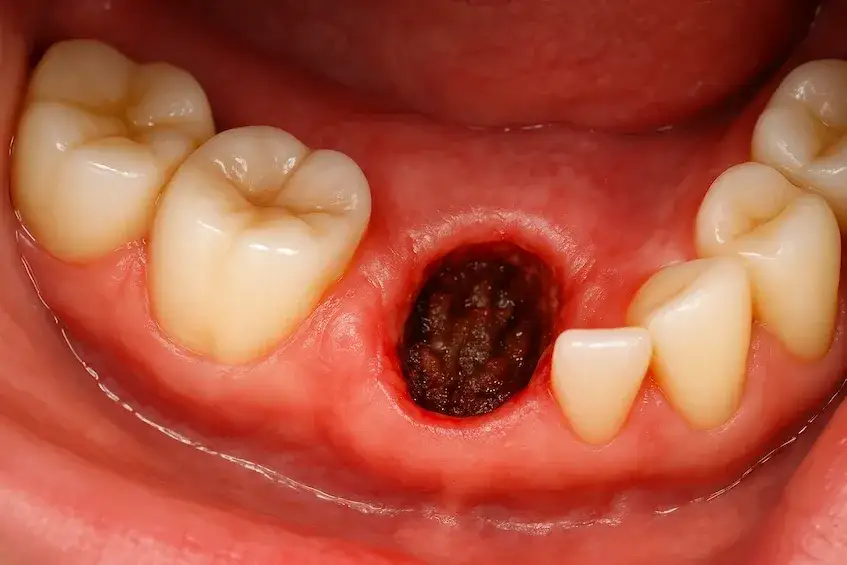

W przypadku wystąpienia objawów suchego zębodołu, ważne jest, aby jak najszybciej podjąć odpowiednie kroki. Objawy, które mogą wskazywać na ten problem, to intensywny ból w okolicy zębodołu, nieprzyjemny zapach z ust oraz widoczna pustka w miejscu usuniętego zęba. Jeśli zauważysz te symptomy, powinieneś niezwłocznie skontaktować się z dentystą, ponieważ ignorowanie objawów może prowadzić do poważniejszych komplikacji. Wczesna interwencja jest kluczowa dla skutecznego leczenia i złagodzenia bólu.

Ważne jest również, aby zrozumieć różnice między normalnym procesem gojenia a objawami suchego zębodołu. Podczas normalnego gojenia ból powinien stopniowo ustępować, natomiast w przypadku suchego zębodołu ból może się nasilać. Poniżej znajduje się tabela, która pomoże Ci zrozumieć, kiedy należy zgłosić się do dentysty.

Rozpoznanie objawów suchego zębodołu jest kluczowe dla szybkiej interwencji. Jeśli odczuwasz intensywny ból, który nie ustępuje, oraz zauważysz nieprzyjemny zapach z ust, powinieneś jak najszybciej zgłosić się do dentysty. Inne objawy, które mogą wskazywać na ten problem, to widoczna pustka w miejscu ekstrakcji oraz obrzęk. Im szybciej podejmiesz działania, tym większe masz szanse na uniknięcie poważniejszych komplikacji związanych z gojeniem.